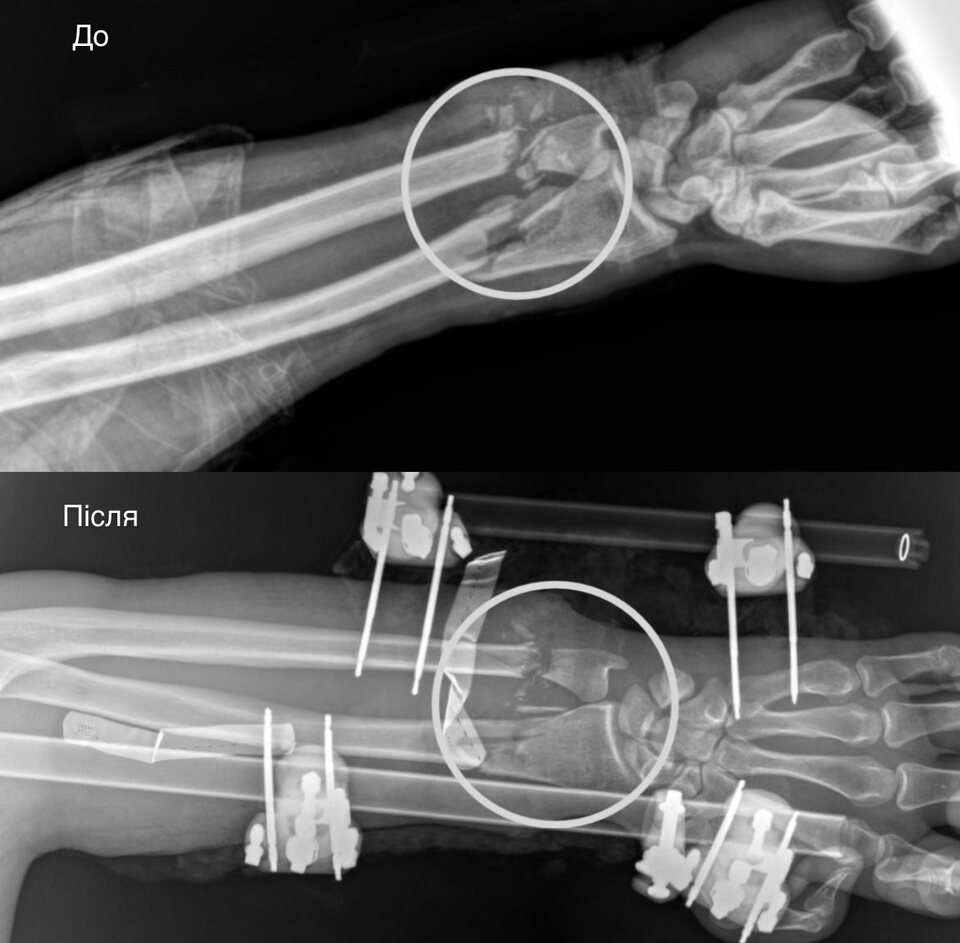

Травма була настільки тяжкою, що рука фактично була ампутованою: бензопила пошкодила артерії, кістки, сухожилля, м’язи та нерви. Порятунок відбувався у кілька вирішальних етапів:

стабілізація кісток: Ортопеди-травматологи зафіксували переломи за допомогою апарата зовнішньої фіксації.

відновлення кровообігу: Судинні хірурги зшили пошкоджені судини. Цей етап був критичним, адже без циркуляції крові тканини почали б відмирати, що зробило б ампутацію неминучою.